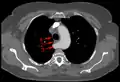

Aberrant subclavian artery at axial CT-scan. (1) trachea, (2) esophagus, (3) Aberrant subclavian artery.